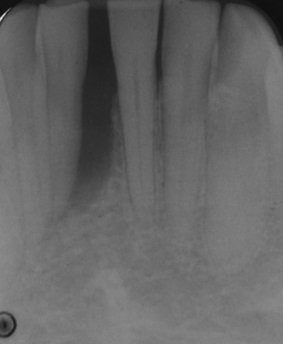

En la radiografía 1 (antes del tratamiento regenerativo) se ve una gran pérdida de hueso alrededor del incisivo inferior (espacio oscuro alrededor de la raíz), provocando prácticamente la caída del diente. El paciente acude a nuestra consulta a solicitar una segunda opinión, ya que la valoración anterior, dado el mal pronóstico del diente, propuso la extracción del mismo.

- Radiografía 1